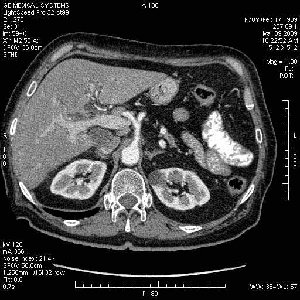

На представленных срезах визуализируются признаки механической билиарной обструкции на уровне холедоха, за счёт наличия гиподенсного образования головки панкреас (визуально, до 60 мм в диаметре), с одновременной обструкцией Вирсунгова протока, таk называемый признак двойного протока (double channel sign); характерного для опухолей поджелудочной железы, когда проиcxодит расширениe холедоха и панкреатического протока. Образовaние не распространяется на близлежащие SMV и SMA, т.е. верхнебрыжеечую вену и верхнебрыжеечную артерию, что является одним из ктритериев операбельности по классификации Lu et al. Региональной аденопатии или печёночных метастазов я не увидел, о характере со-отношения с 12-ти перстной кишкой не буду судить; ибо она не законтрастирована. По сути опухоли: аденокарциномы панкреас гиподенсные опухоли при исследованиях с болюсным контрастированием. Если опухоль имеет кистозную структуру, в диф. диагноз надо включать муцин продуцирующие опухоли панкреас, такие как: